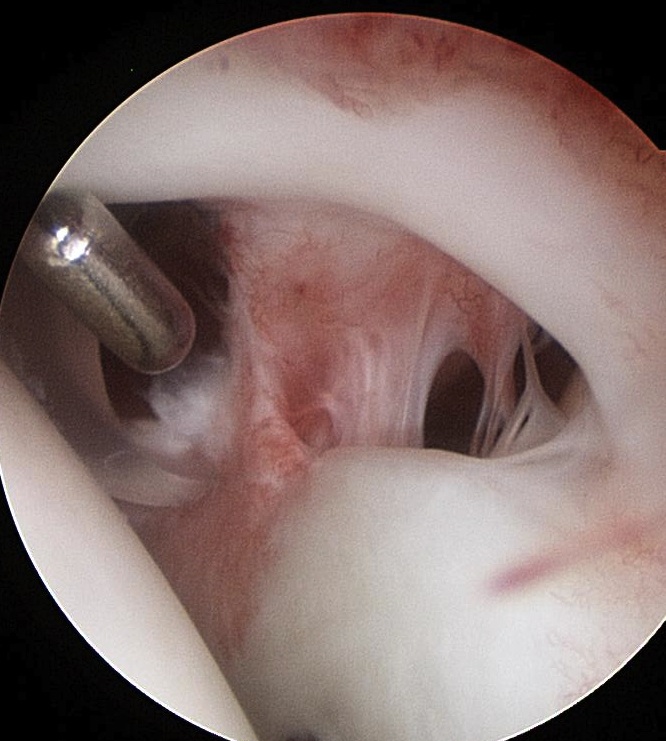

Open subpectoral biceps tenodesis

Technique

Beachchair

- arthroscopic biceps tendon release

- SLAP repair

- open approach to biceps

- incision centered on humerus below pectoralis tendon

- retract deltoid laterally / elevate pectoralis tendon / conjoint tendon medially

- find biceps tendon / shorten to 2cm of tendon / suture

- anchor biceps tendon

Bicortical open subpectoral biceps tenodesis using Arthrex Biceps Button